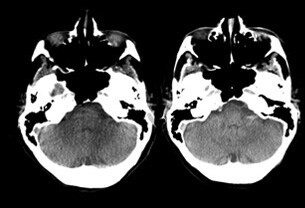

Our innovative Neuro suite is already delivering advancements in interventional neuroradiology, such as our industry-leading CT-like SmartCT which provides excellent imaging quality to assist interventional neuroradiologists with diagnosis and treatment.

We are currently conducting clinical studies at several leading stroke sites to evaluate new acquisition protocols and assess imaging quality (artefact reduction and image reconstruction) of CBCT (Cone-Beam CT) scans in patients with neurovascular diseases, and assess impact on the workflow compared to the standard of care.6